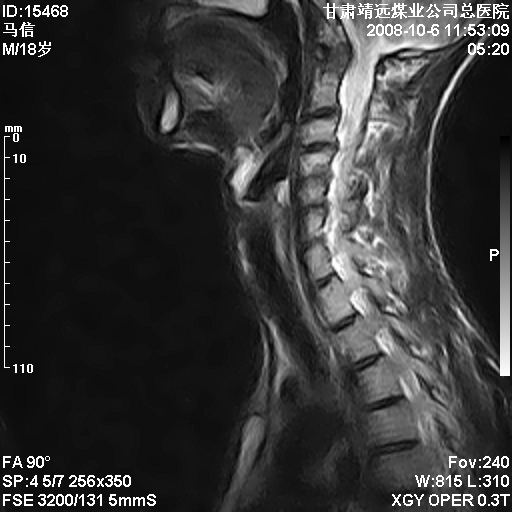

标题: MRI1827:颈椎内异常信号,是不是占位。

患者18岁,学生,在玩耍中受伤来检查,患者喜欢打篮球。颈椎内异常信号影,我们考虑占位,但是不像占位,又考虑硬膜囊的增厚,大家关建看颈椎椎管内的那个异常占位信号

腰椎的改变是不是正常发育的改变,还是打篮球的长期慢性损伤。

颈椎建议做增强扫描;腰椎诸椎终板骨骺炎。

后纵韧带增厚,颈2/3、3/4、4/5、5/6椎间盘变性、突出;椎体有旋转,提示椎小关节有问题;腰椎间盘变性,许莫氏结节。

后纵韧带增厚,颈2/3、3/4、4/5、5/6椎间盘变性、突出;椎体有旋转,提示椎小关节有问题。腰椎诸椎体终板骨骺炎可能性大!支持!

椎体终板骨骺炎可能性大!支持!